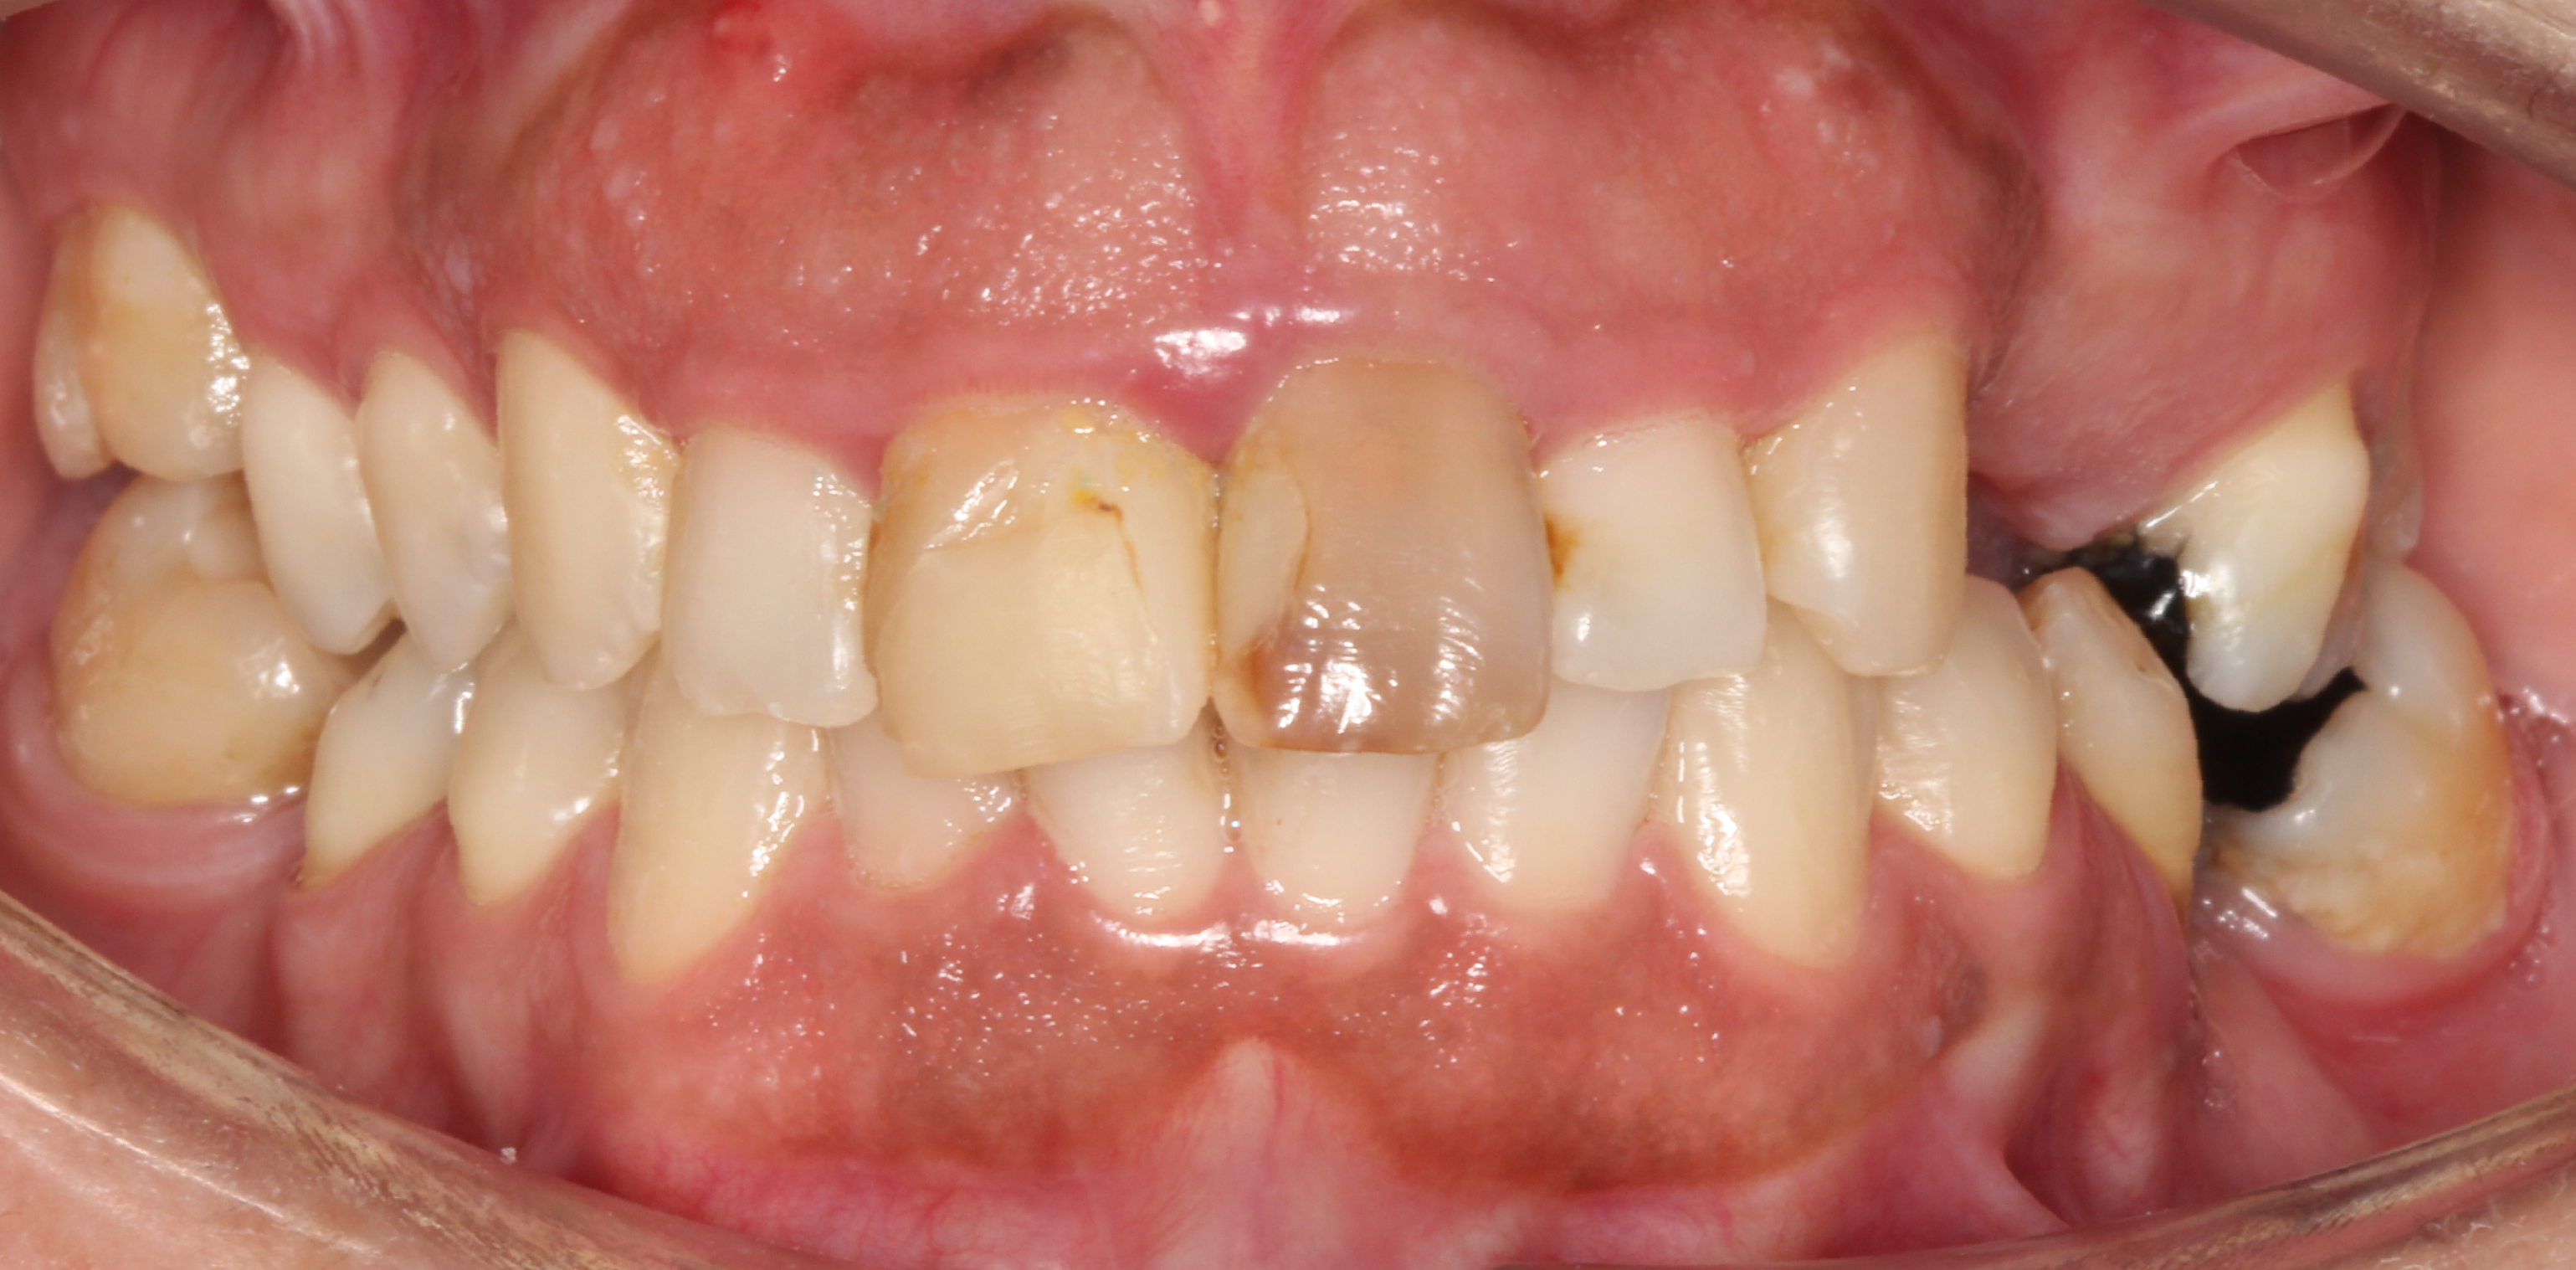

Há casos em que a junção de diferentes tratamentos estéticos é o ideal para conseguir os melhores resultados. No caso que apresentamos aqui, o estado inicial do sorriso da paciente exigia que houvesse uma correção no alinhamento dos dentes antes de poder adereçar qualquer outro problema apresentado. Assim, começámos por idealizar um planeamento, para perceber os passos que o tratamento iria seguir do início ao fim, já que uns procedimentos influenciam diretamente os outros.

Sorriso da paciente antes de iniciar qualquer tratamento.